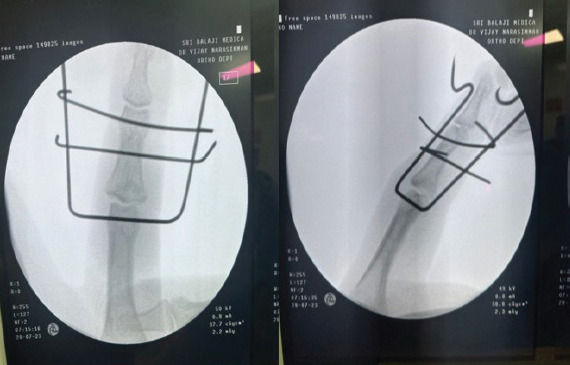

Case report: A 37-year-old male sustained an intra-articular middle phalanx base fracture with dorsal subluxation of the left index finger during a cricket injury. Examination showed swelling, tenderness, and a flexion deformity. Radiographs confirmed a comminuted volar lip fracture. Under fluoroscopic guidance, a Suzuki frame was applied using three K-wires and rubber band traction. Advanced imaging was not deemed necessary for acute management. Early active motion was initiated post-operatively, followed by a structured hand therapy protocol. At 6 months, radiological union, >90% range of motion, minimal pain, and return to function were achieved.